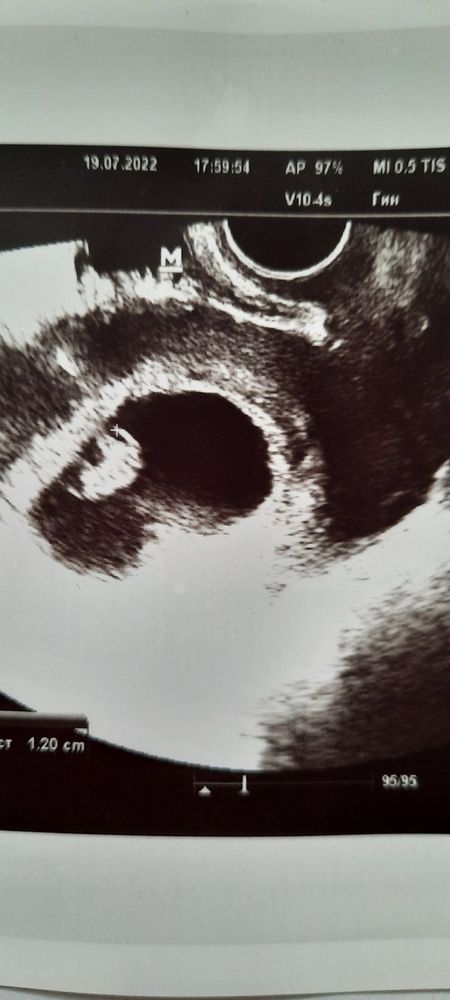

Добрый день,милые беременюшки!Ну вот я снова с вами, хотя уже думала,что на третьем сынуле остановлюсь....но вот судьба решила иначе.Первый раз без приёма гормонов,без подготовки к беременности,Бог наградил нас ещё одной пуговкой)))Помогите,пожалуйста, определить кого на этот раз ждём, мальчика или девочку по методу Рамзи?Узи на 7-8 недели беременности, трансвагинально. УЗНАЮ ОАДИ ИНТЕРЕСА,РЕБЕНОК БУДЕТ ЛЮБИМ КАК И ВСЕ ОСТАЛЬНЫЕ ДЕТИШКИ!